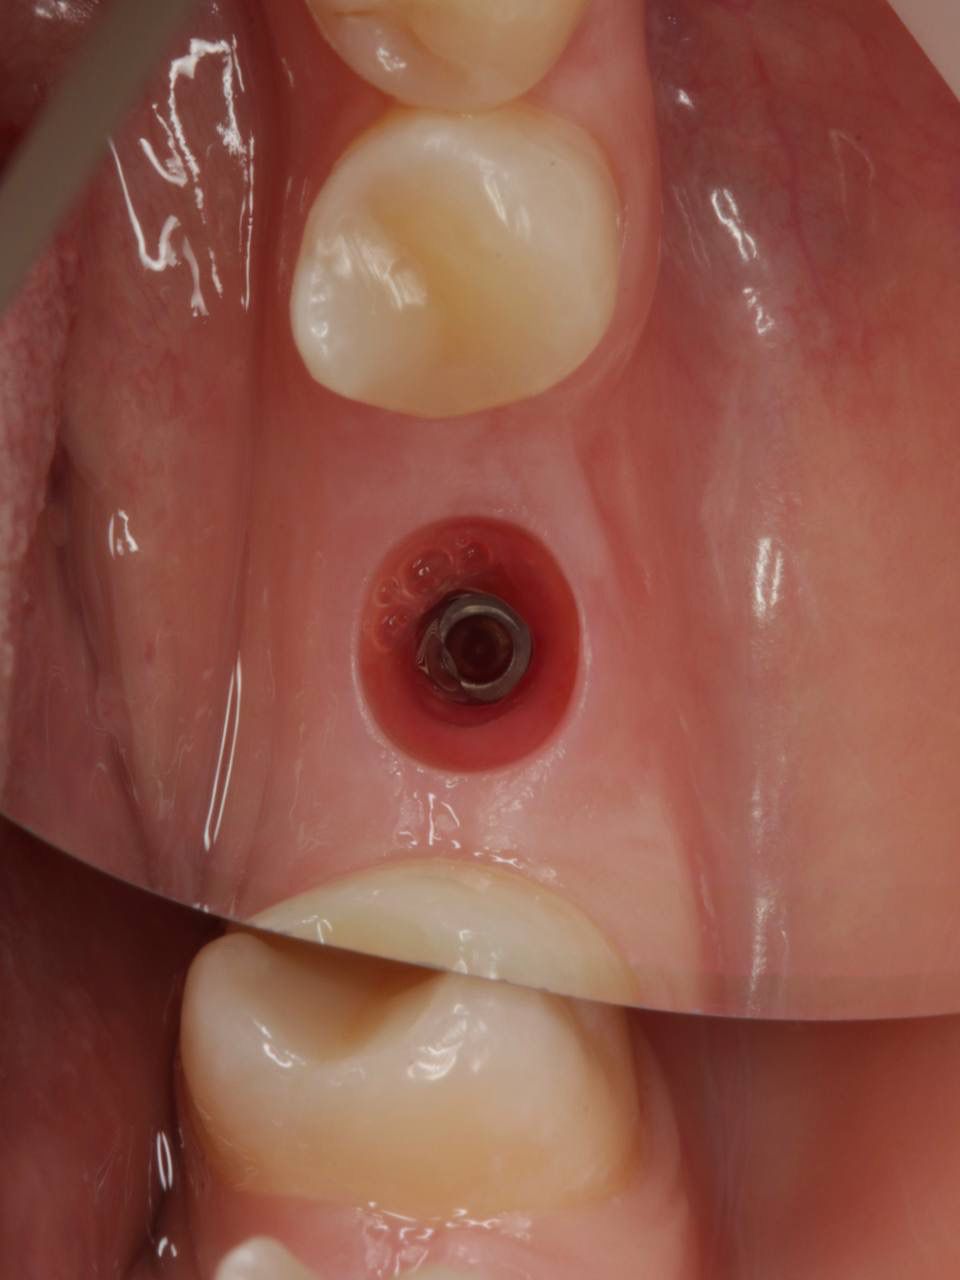

Одномоментная имплантация системой Osstem(Ю. Корея), подшит трансплантат с бугра(для увеличения объема мягких тканей), установлен формирователь десны. Через 3 месяца установлена коронка из диоксида циркония на винтовой фиксации